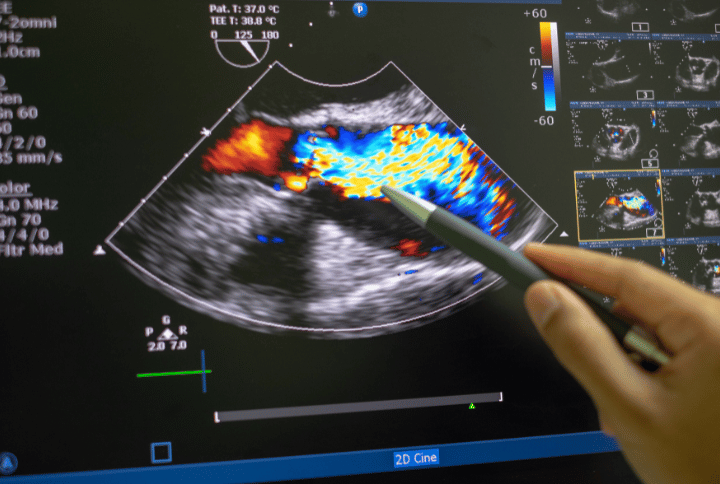

Doppler Studies

Doppler ultrasound helps assess blood flow through arteries and veins, ensuring early diagnosis of vascular conditions. Whether it’s obstetric doppler for fetal well-being, venous/arterial doppler for limb circulation, or renal/portal dopplers, our studies offer vital insights into circulatory health. These scans support timely medical decisions with precise, real-time blood flow analysis.